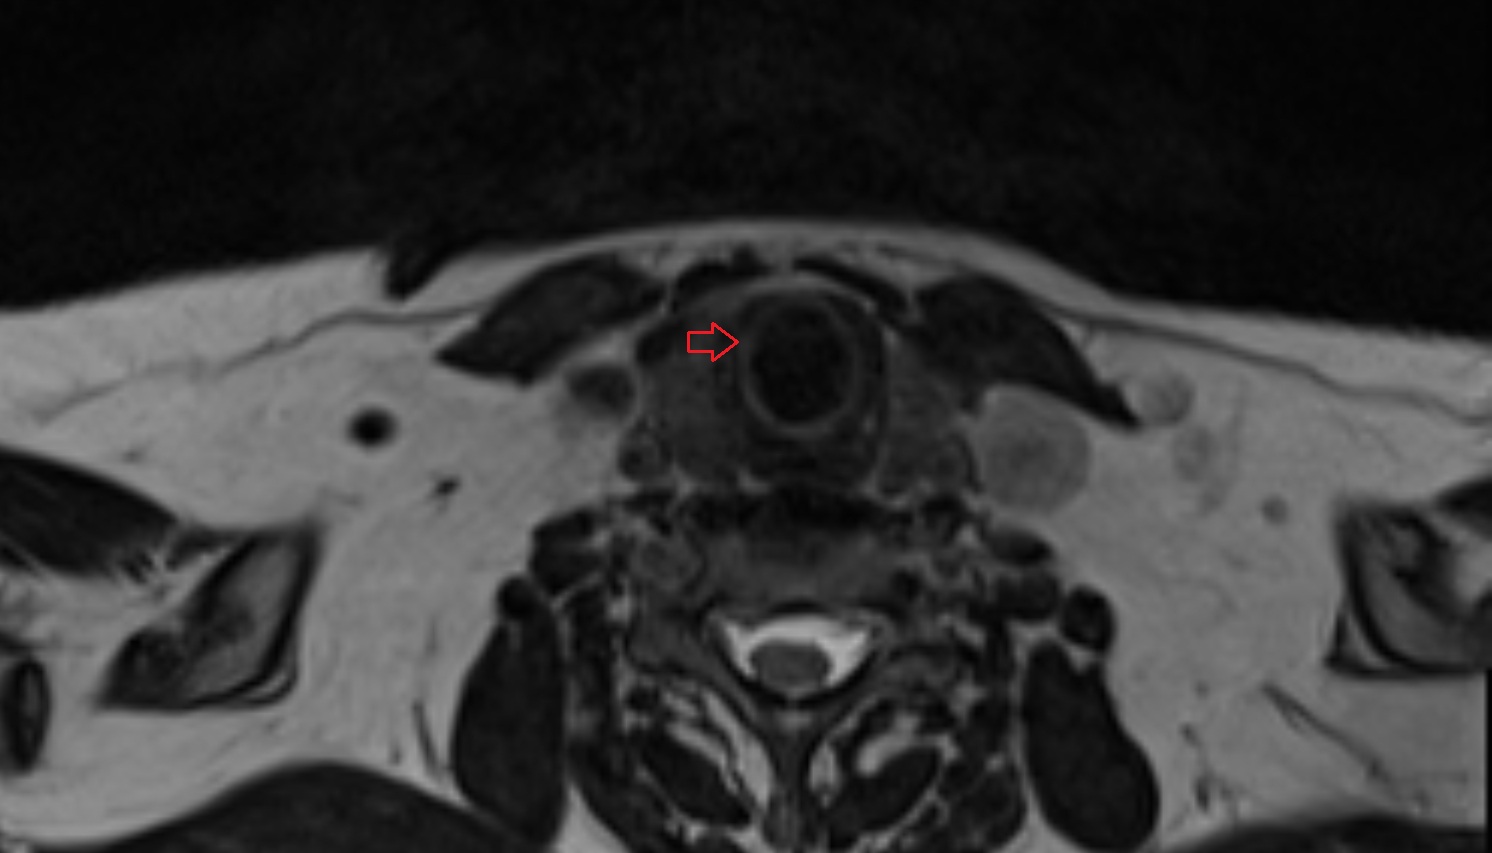

- Peripheral zone of prostate

- Anterior Fibromuscular Stroma of prostate

- Central zone of prostate

- Transitional zone of prostate